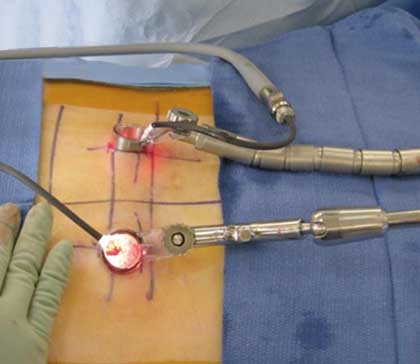

Minimally invasive spine surgery (MISS) is a type of surgery on the bones of your spine (backbone). This type of surgery uses smaller incisions than standard surgery. This often causes less harm to nearby muscles and other tissues. It can lead to less pain and faster recovery after surgery.

The standard method of spine surgery is called open surgery. This uses a long incision down the back. The muscles and soft tissue around the spine would need to be moved away. In some cases, tissue would need to be removed.